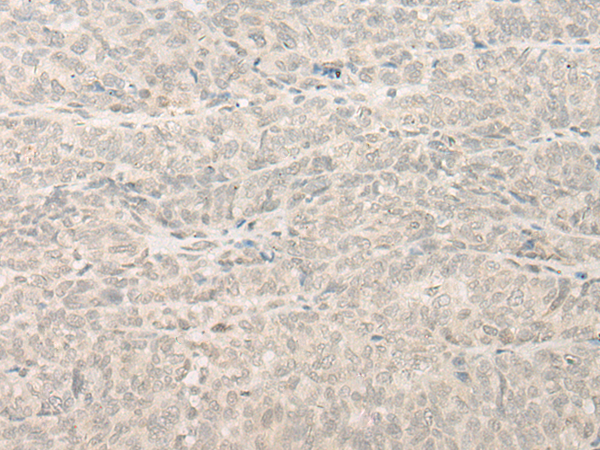

分类: 科研抗体货号: P09618别名: FAM31A; KIAA1608应用: IHC反应种属: Human